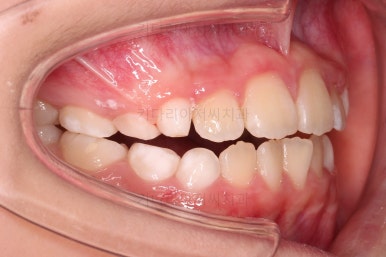

마찬가지로 초진 시 입안의 모습이에요.

아래 앞니가 윗니보다 앞에 있는 "반대교합" 즉, 거꾸로 물려있는 상황이었고요.

어금니 쪽을 보시면(왼쪽 위 사진) 윗니 어금니도 아래 어금니보다 안쪽으로 들어와 있는 "어금니 반대교합"도 있는 상황이었어요.

즉, 윗니가 있는 위턱뼈가 3차원적으로 작은 상황이었던거죠.

이렇게 아랫니들이 윗니보다 앞으로 나와있는 형태의 부정교합을 "앵글씨 3급" 부정교합이라고 합니다.